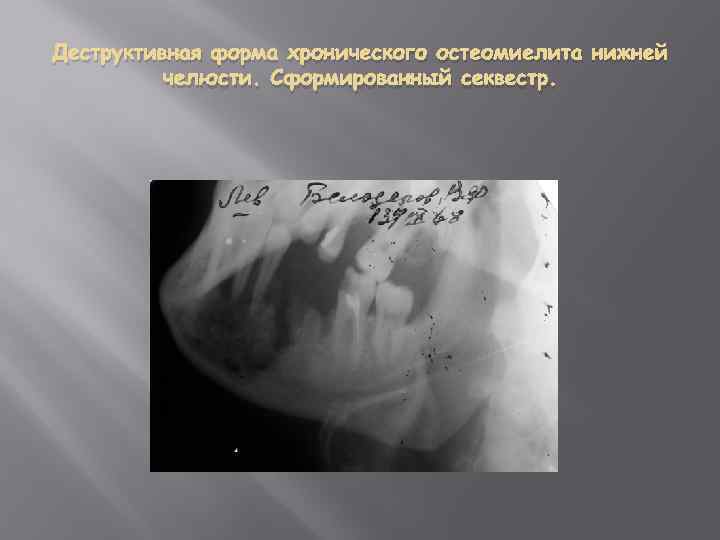

Деструктивная форма хронического остеомиелита нижней челюсти. Сформированный секвестр.